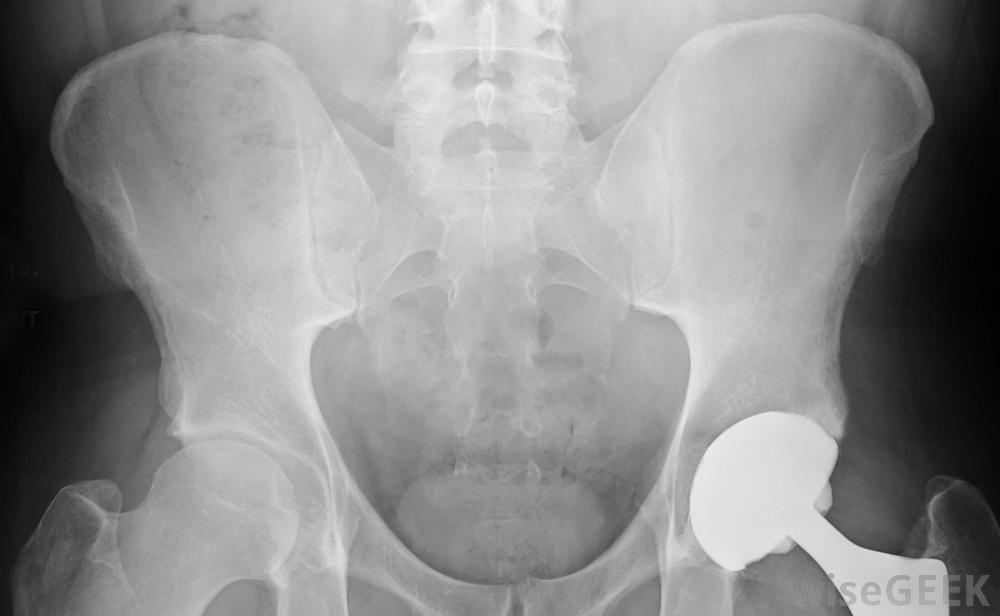

比起人工髋关节置换髋关节,管理撞击更为可取。这种情况可分为两种类型之一,即凸轮和钳形撞击,但也可能是两者的结合Cam股骨髋臼撞击是指股骨头形状的异常,理想情况下应该是球形的,这样的异常会导致股骨骨刮到关节窝上,从而损伤作为两块骨头之间缓冲的关节内软骨

在髋关节受伤后,患者可能需要重建平衡技能。在许多情况下,两种髋臼撞击均存在:异常股骨头在窝内过度摩擦,髋臼覆盖了太多的股骨表面积。这种情况的可能性在活跃个体中增加,在参加某些运动如体操的人中更为明显。股骨的治疗髋臼撞击取决于病情的严重程度,可从疼痛和生活方式管理到手术。保守治疗可包括物理治疗和非处方止痛药,而手术选择包括关节镜和传统手术,取决于股骨头是否,髋臼或关节角度需要修改无论推荐的治疗方法是什么,其目标通常是推迟或阻止髋关节置换术的进行。